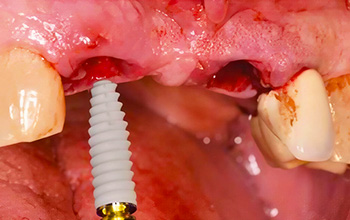

Les racines défaillantes ont été extraites de manière atraumatique (21 et 12).

Fig. 3 : Extraction atraumatique de la 12 et 21.

Deux implants CAMLOG® PROGRESSIVE-LINE de 3,8 mm × 13 mm ont été posés dans les alvéoles d’extraction.